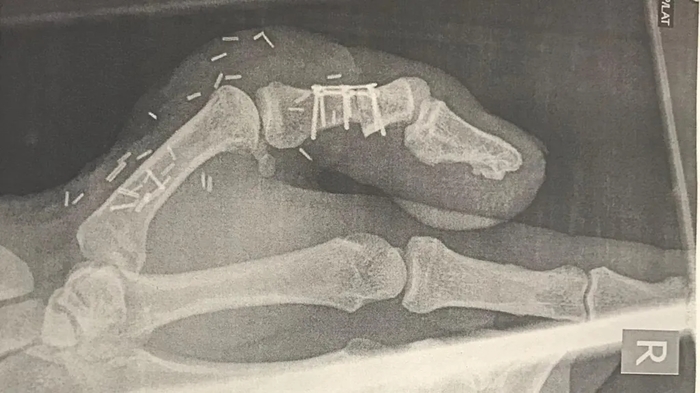

616512c0-f79f-11f0-86b9-f9a693442abd.jpg엄지손가락 절단 사고를 겪은 데이비드 리의 엑스레이 사진. / BBC